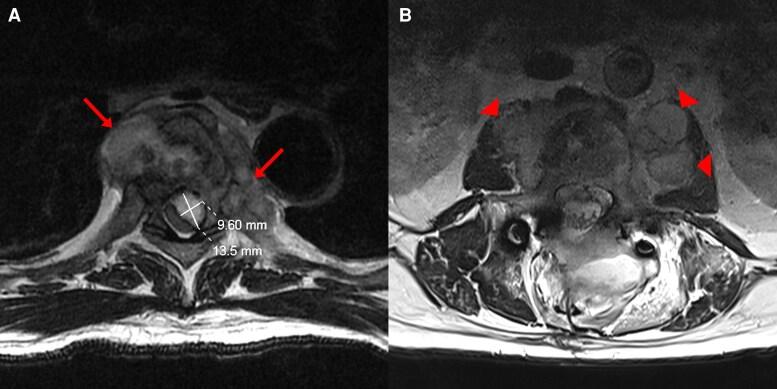

can infect the native vertebral body and nearby structures to cause tuberculous spondylodiscitis, also known as Pott disease. We present a case of extensive, multifocal Pott disease in a United States-born veteran without human immunodeficiency virus. We briefly comment on when to consider Pott disease in cases of vertebral osteomyelitis. We also discuss treatment considerations for Pott disease with and without tuberculous involvement of the central nervous system, the recognition of tuberculosis-associated immune reconstitution inflammatory syndrome, and certain indications for surgery in Pott disease.

可感染原生椎体及附近结构,导致结核性脊椎间盘炎,也称为波特病。我们报告一例在美国出生、无人类免疫缺陷病毒的退伍军人发生广泛、多灶性波特病的病例。我们简要评论在椎体骨髓炎病例中何时应考虑波特病。我们还讨论了波特病伴或不伴有中枢神经系统结核感染时的治疗考量、结核相关免疫重建炎症综合征的识别以及波特病的某些手术指征。